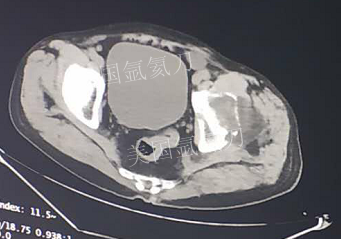

73岁臀部氩氦刀冷冻消融